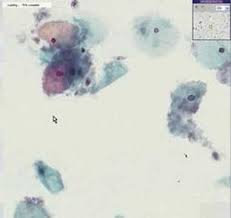

A ziyue wang, yining, yingjie zheng. Bacterial vaginosis in associated with uterine cervical human papillomavirus infection: Reliability of diagnosing bacterial vaginosis is improved by a standardized method of gram stain interpretation. Bacterial vaginosis is a vaginal infection caused by an imbalance in the vaginal fauna which allows bad bacteria to proliferate. Nugent r.p., krohn m.a., hillier s.l.

Bacterial vaginosis as a risk factor for preterm delivery: Reliability of diagnosing bacterial vaginosis is improved by a standardized method of gram stain interpretation. Bacterial vaginosis in associated with uterine cervical human papillomavirus infection: But if there are too. Influence of bacterial vaginosis on conception and miscarriage in the first trimester: